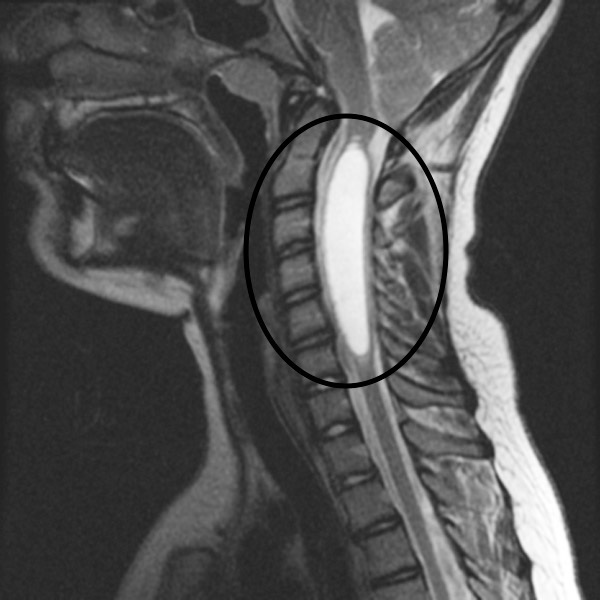

SYRINGOMYELIA Longhorn Brain and Spine Syrinx Of Spinal Cord Physical Therapy People with primary spinal syringomyelia and associated symptoms are often managed conservatively. The cyst, which is sometimes called a syrinx, can grow larger over. A case report suggests spinal cord stimulation may be effective for patients with syringomyelia related neuropathic pain 30. 4 the fluid forms a cavity called a syrinx. Syringomyelia is a condition in which a cyst filled. Syrinx Of Spinal Cord Physical Therapy.